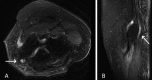

Figure 3. Axial (A) and Sagittal (B) MRI of the left elbow reveals thickening and increased signal intensity of the ulnar nerve proximally and at the level of the cubital tunnel, consistent with ulnar neuritis/cubital tunnel syndrome.